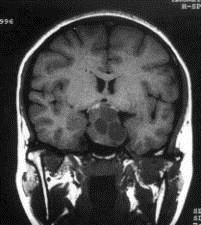

问题 病历摘要:??患者男性,35岁。性功能减退2年,视力下降6月。既往体健。体检:神清,皮肤细腻,毛发稀疏。视力左眼0.3,右眼0.5,双瞳等大等圆,直径3.5mm,对光反射稍迟钝,双颞侧偏盲,双眼底视神经乳头原发性萎缩,余神经系统未见异常。 入院后应申请哪些辅助检查?

选项 A.内分泌功能检查 B.脑电图 C.头颅平片 D.头颅MR E.TCD F.SPECT G.CT H.PET

答案 ACDG